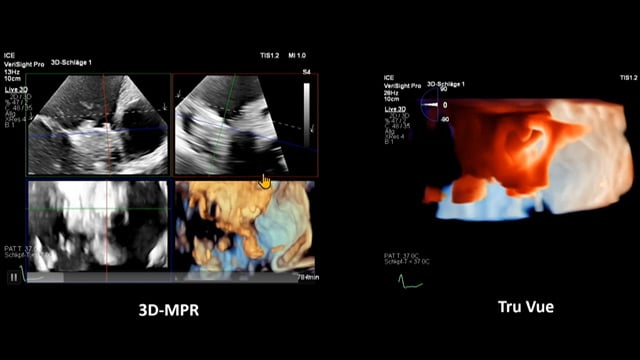

The next frontier in LAA closure: innovations and opportunities

17 Nov 2025 – From PCR London Valves 2025

Explore the forefront of left atrial appendage (LAA) closure with this session focusing on the latest innovations and clinical opportunities. Topics include recent data on WATCHMAN FLX PRO and VersaCross Connect systems, workflow strategies to improve procedural efficiency, and discussions on upcoming clinical trials such as...